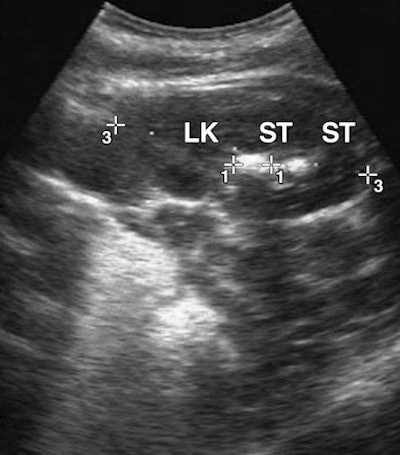

| Ten-month-old male infant with seven-day history of dysuria and vomiting who had been exposed to infant milk formula contaminated with melamine and cyanuric acid for 10 months. Sonography images show multiple hyperechoic calculi in bilateral kidneys. LK = left kidney, ST = stone. |

Diagnostic imaging displayed calculi formation of the urinary tract, with calculi varying greatly in size and shape, according to the authors. Fourteen patients had multiple calculi and 12 patients had bilateral calculi. A total of 51 calculi were identified.

The 37 renal calculi observed were oval, staghorn, or punctiform and were not measured because they varied greatly in size and shape. The 14 ureteral calculi were oval in shape and averaged 8 x 5 mm in size, with a range of 4 x 3 mm to 11 x 8 mm.

The calculi formation of the urinary tract also caused hydronephrosis, the cystic distension of the kidney. Seventeen kidneys in 13 patients were affected. The calculi that led to hydronephrosis were located in the ureteropelvic junction (eight kidneys), renal pelvis (five kidneys), stricture cross of the branch of the iliac artery (two kidneys), and ureterovesical junction (one kidney). Two of the patients had overfilled bladders and one patient had a perirenal hematoma.